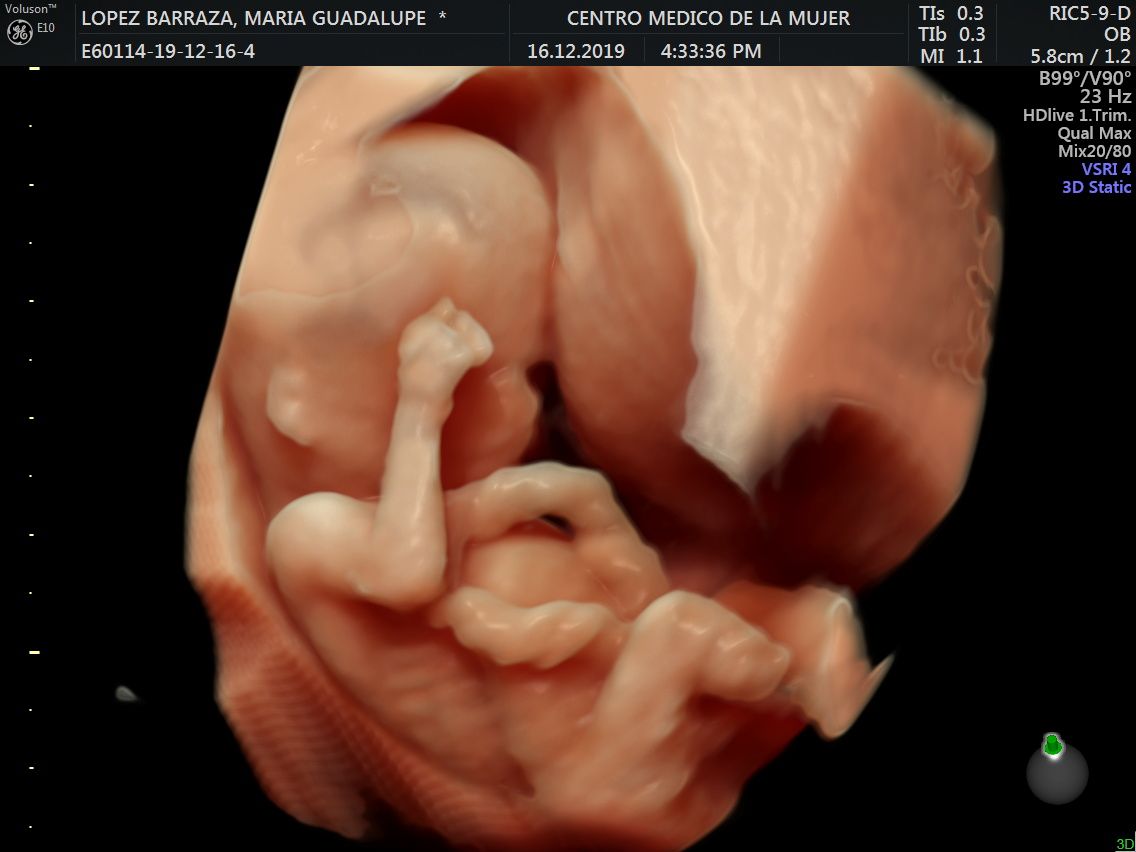

Fotos y videos

ECO Anatómico

Consiste en la evaluación especifica de cada organo y sistema del bebé con medidas detalladas de cada parte para evaluar su crecimiento proporcional.